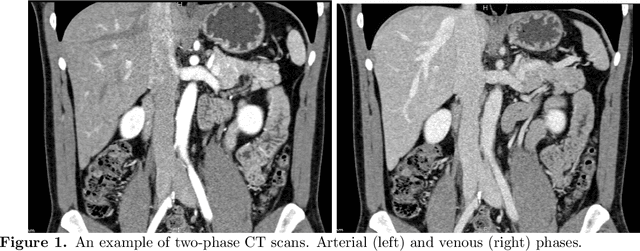

Abstract:Pancreatic ductal adenocarcinoma (PDAC) is one of the most lethal cancers among population. Screening for PDACs in dynamic contrast-enhanced CT is beneficial for early diagnose. In this paper, we investigate the problem of automated detecting PDACs in multi-phase (arterial and venous) CT scans. Multiple phases provide more information than single phase, but they are unaligned and inhomogeneous in texture, making it difficult to combine cross-phase information seamlessly. We study multiple phase alignment strategies, i.e., early alignment (image registration), late alignment (high-level feature registration) and slow alignment (multi-level feature registration), and suggest an ensemble of all these alignments as a promising way to boost the performance of PDAC detection. We provide an extensive empirical evaluation on two PDAC datasets and show that the proposed alignment ensemble significantly outperforms previous state-of-the-art approaches, illustrating strong potential for clinical use.